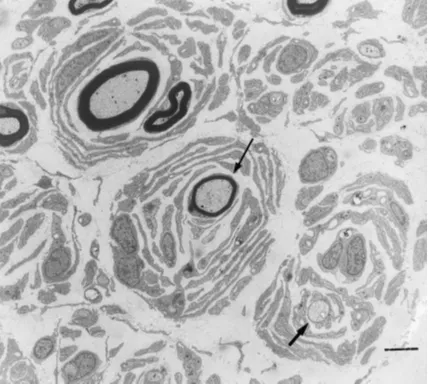

Наиболее распространенным подтипом заболевания является БШМТ 1А типа, который относится к демиелинизирующей сенсорно-моторной нейропатии и составляет около 60-70% всех случаев. В основе патогенеза данного заболевания лежит дупликация участка короткого плеча 17 хромосомы (17р11.2-12), на котором располагается ген PMP22, кодирующий периферический миелиновый белок 22 (peripheral myelin protein - PMP22). Белок PMP22 является главным компонентом миелиновой оболочки, составляет порядка 2-5% миелина в периферической нервной системе и продуцируется преимущественно Шванновскими клетками. В результате увеличения копийности гена PMP22 происходит увеличение количества данного белка. Однако известно, что концентрация PMP22 у пациентов с БШМТ 1А типа с течением времени может колебаться и достигать нормальных значений. Это может быть объяснено сменяющими друг друга периодами демиелинизации и ремиелинизации, которые имеют место при данном заболевании. В результате пролиферации Шванновских клеток образуются так называемые «луковые кольца».

Рис 2. БШМТ 1А. Феномен «луковых колец». Поперечный разрез аксональной части нейронов. В одном случае миелиновая оболочка аномально тонкая по сравнению с размером аксона (тонкая стрелка). В другом случае «голый» аксон окружен концентрической пролиферацией шванновских клеток (жирная стрелка). Масштабная линейка: 4 мкм [4].